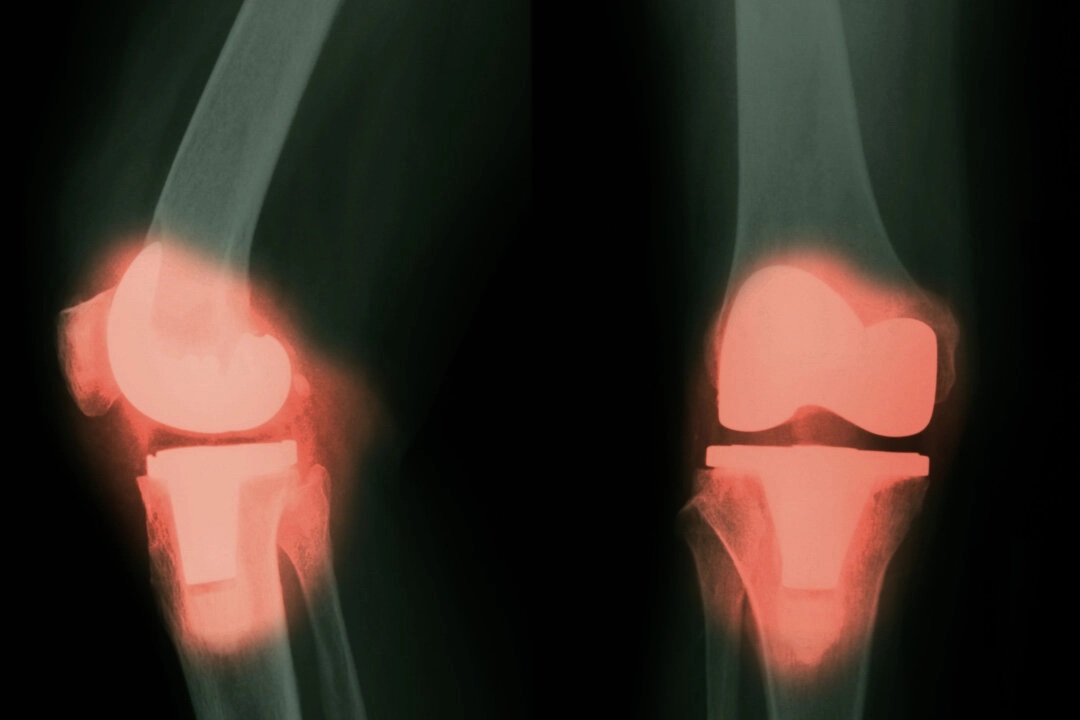

一項新研究發現,有些接受過常規大型關節置換手術的患者,其血液、大腦和脊髓液中的某些金屬含量會升高,這引發了人們的擔憂:體內金屬含量的升高是否會對神經系統造成長期的不良反應。

在美國,每年大約進行79萬例全膝關節置換手術和54.4萬例髖關節置換手術,預計隨著人口老齡化,這些數字還將繼續上升。

目前,鈦和鈷-鉻合金是製造假體關節最常用的金屬材料。鈷-鉻-鉬合金以其強度高、耐用性強和抗腐蝕能力強而聞名,因此被廣泛用於金屬關節置換中,特別是在髖關節和膝關節假體中。不過,這些關節也可能包含陶瓷材料,像是氧化鋁和氧化鋯。在某些組件中,特別是髖關節假肢中,這些陶瓷材料可以提高耐磨性和生物相容性。